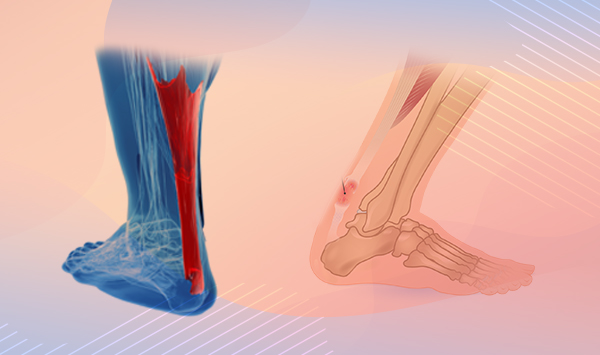

Тендинит Ахиллова сухожилия: симптомы и лечение

Раздел: Картинки на заметку